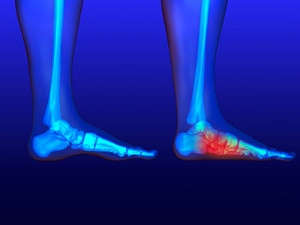

Flatfoot is a condition in which the arch of the foot is depressed and the sole of the foot is almost completely in contact with the ground. About 20-30% of the population generally has flat feet because their arches never formed during growth.

Having flat feet makes it difficult to run or walk because of the stress placed on the ankles.

Alignment – The general alignment of your legs can be disrupted, because the ankles move inward which can cause major discomfort.

Knees – If you have complications with your knees, flat feet can be a contributor to arthritis in that area.

- Pain around the heel or arch area

- Flat look to one or both feet

- Having your shoes feel uneven when worn

If you are experiencing pain and stress on the foot you may weaken the posterior tibial tendon, which runs around the inside of the ankle.